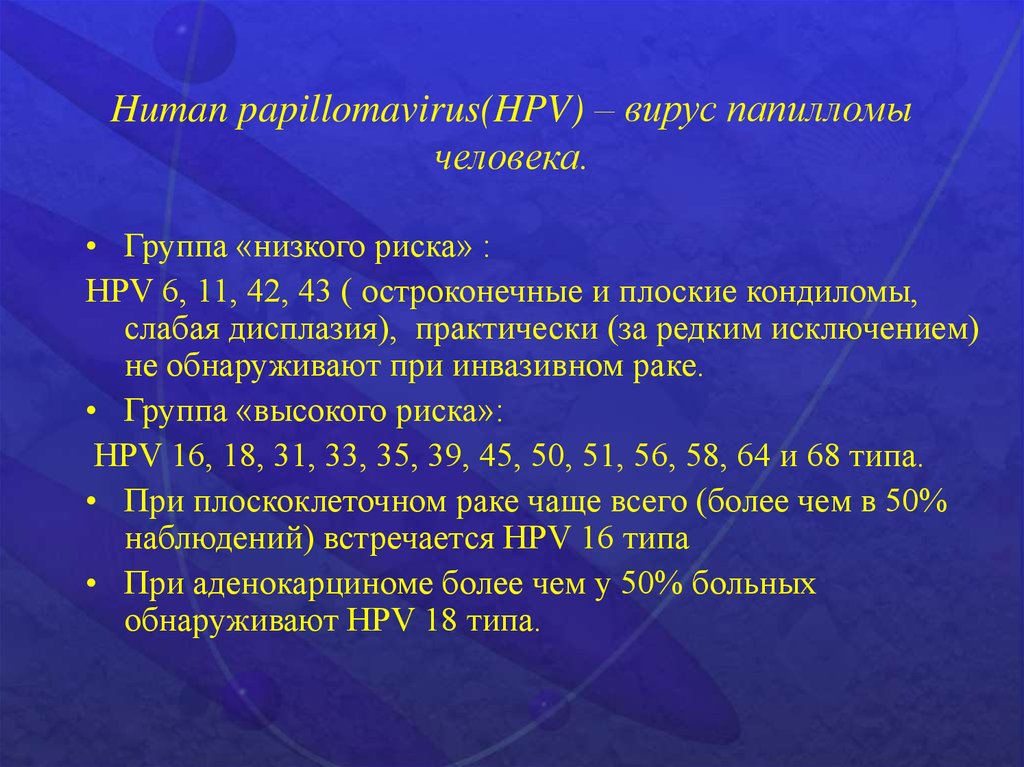

Факторы Риска ВПЧ: Визуальный Обзор и Информация

Раздел: Кладезь мудрости